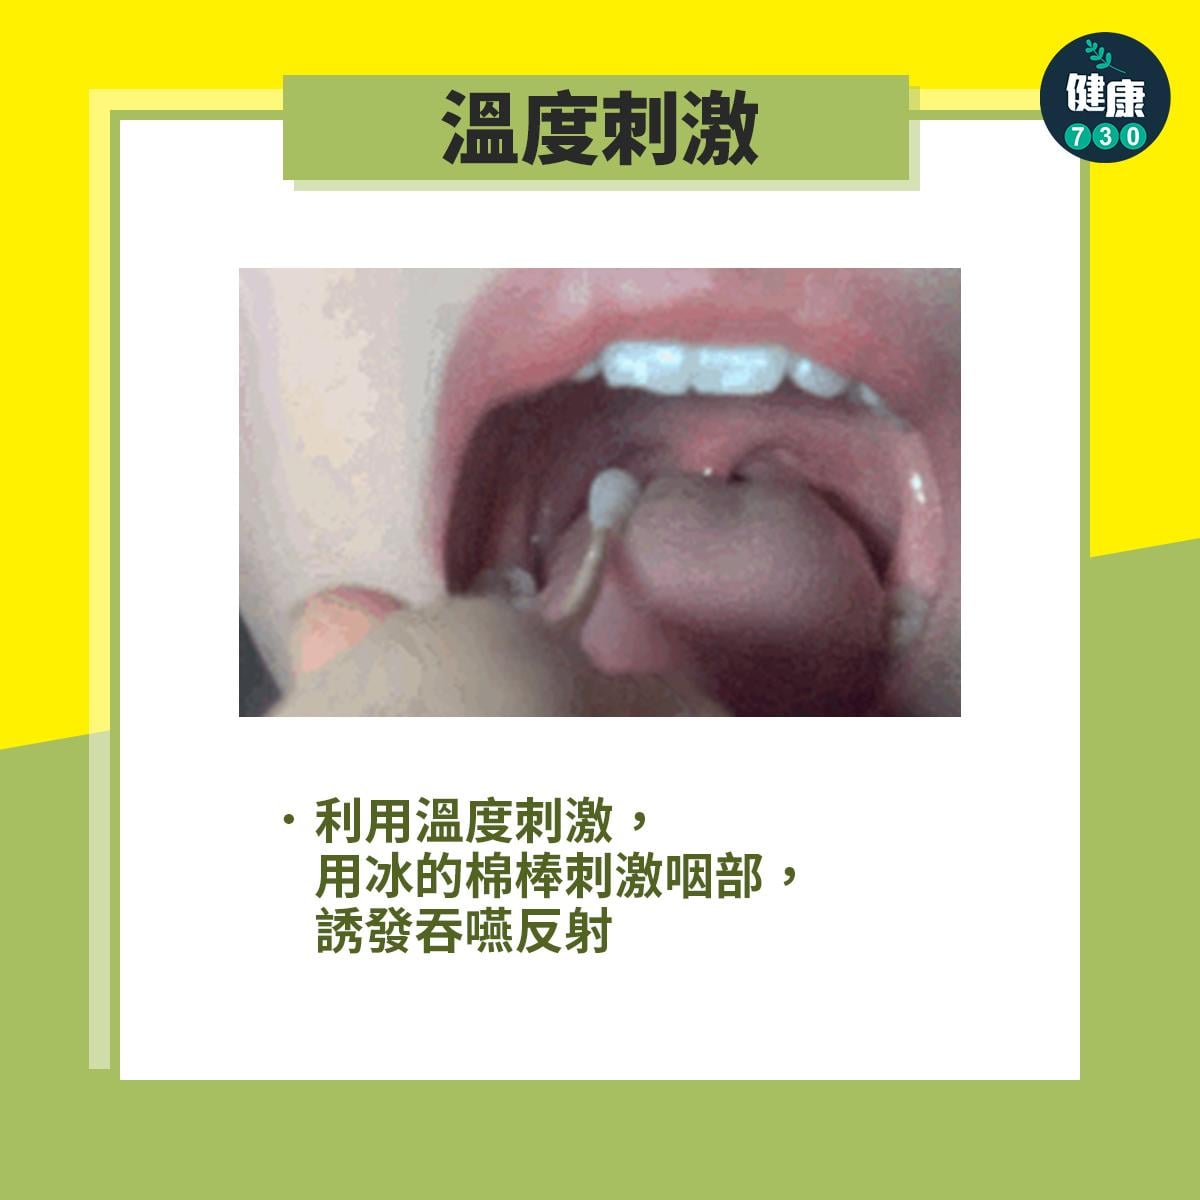

中風復健|5招改善中風後吞嚥困難